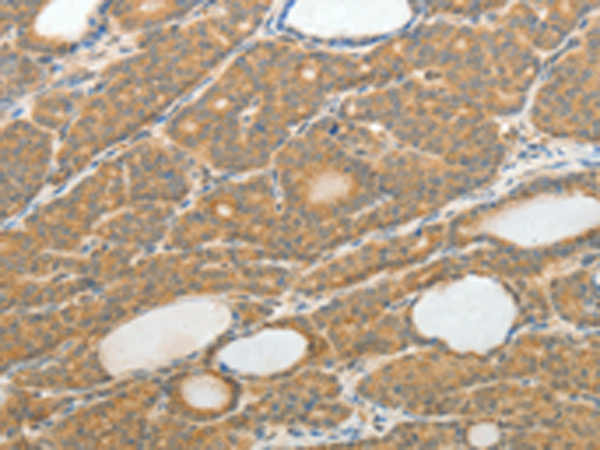

分类: 科研抗体货号: P11131别名: SELS; VIMP; ADO15; SBBI8; SEPS1; AD-015应用: IHC反应种属: Human, Mouse, Rat